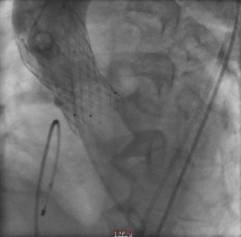

另外一例患者谢爷爷面对一场惊心动魄的“生死战”。首先,在球囊抵达主动脉瓣口,刚准备扩开为瓣膜植入创造条件时,瞬间出现室颤,心跳骤停。“快,除颤、心肺复苏!”团队医护人员迅速抢救,同时另一组人将瓣膜送入心脏,跨瓣压差由术前127mmHg降至术后3mmHg。术后送入ICU治疗,第3天,谢爷爷病情稳定,即可下床活动。